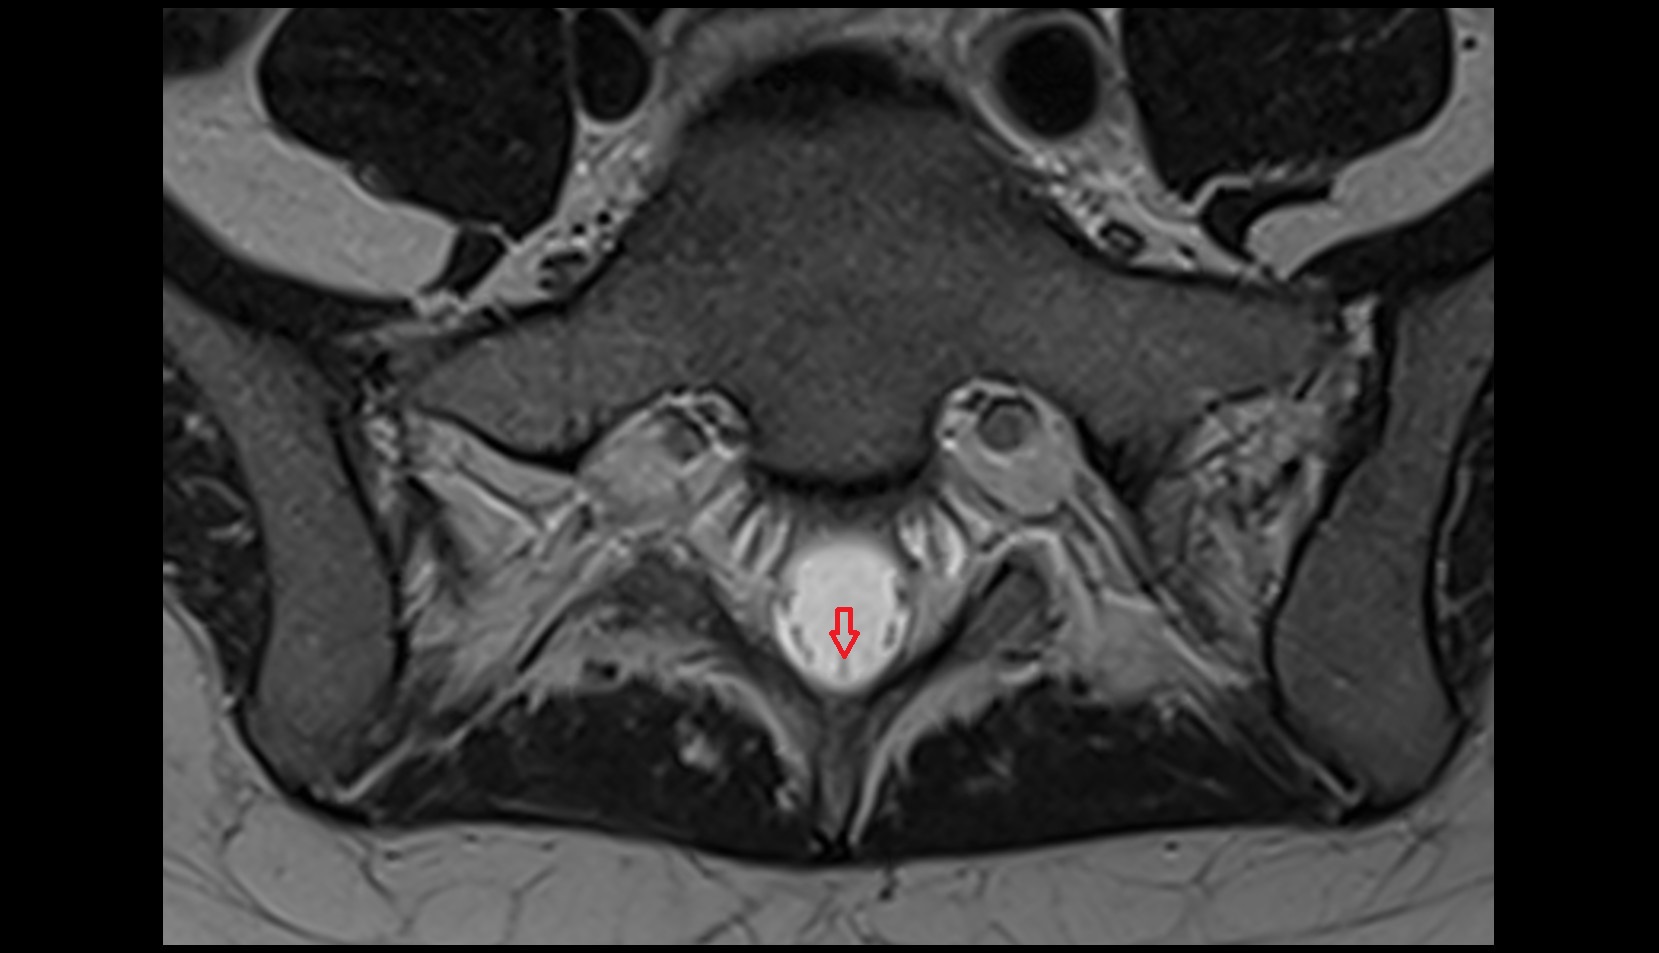

- Peripheral zone of prostate

- Anterior Fibromuscular Stroma of prostate

- Central zone of prostate

- Transitional zone of prostate